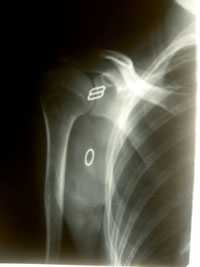

五十肩(肩関節周囲炎)、石灰沈着性腱板炎、上腕二頭筋炎、インピンジメント症候群

腱板損傷、肩峰下滑液包炎、野球肩などたくさんあります。

レントゲン上ではあまり原因を特定できないものです。